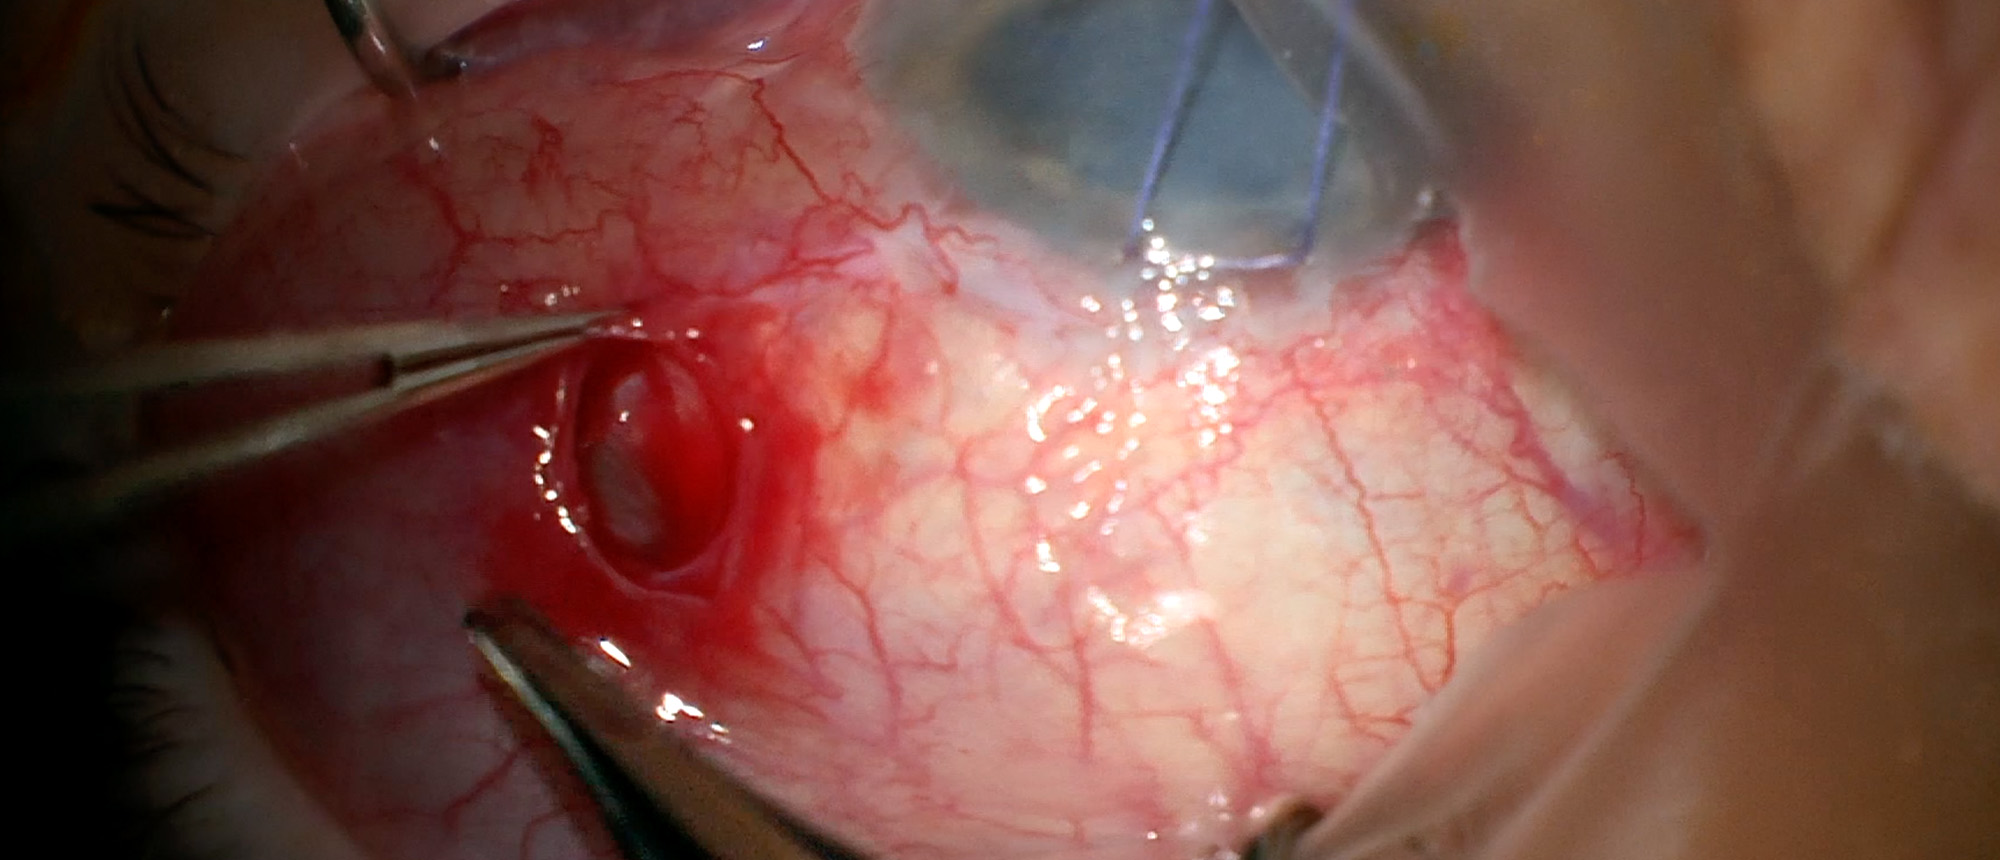

Juvenile Xanthogranuloma

Specialty: Glaucoma

Include in Catalogue?: No

Presenter(s): Lindsay Foley, MD

Faculty Discussant(s): Sander R. Dubovy, MD; Angela Y. Zhu, MD

Abstract A baby was referred for a new-onset subconjunctival lesion in the right eye. He was found to have a thickened, yellow corneoscleral lesion and hyphema, presumed to be ocular juvenile xanthogranuloma (JXG). He was started on topical steroids as empiric treatment, with initial improvement fo…

Juvenile Xanthogranuloma A baby was referred for a new-onset subconjunctival lesion in the right eye. He was found to have a thickened, yellow corneoscleral lesion and hyphema, presumed to be ocular juvenile xanthogranuloma (JXG). He was started on topical steroids as empiric treatment, with initia…

Type: Online Grand Rounds

Include in Catalogue?: Yes

Presenter/Faculty: Dubovy, Foley, Zhu